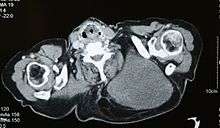

Micrograph of a myxoid liposarcoma. H&E stain.

Micrograph of a dedifferentiated liposarcoma. H&E stain.